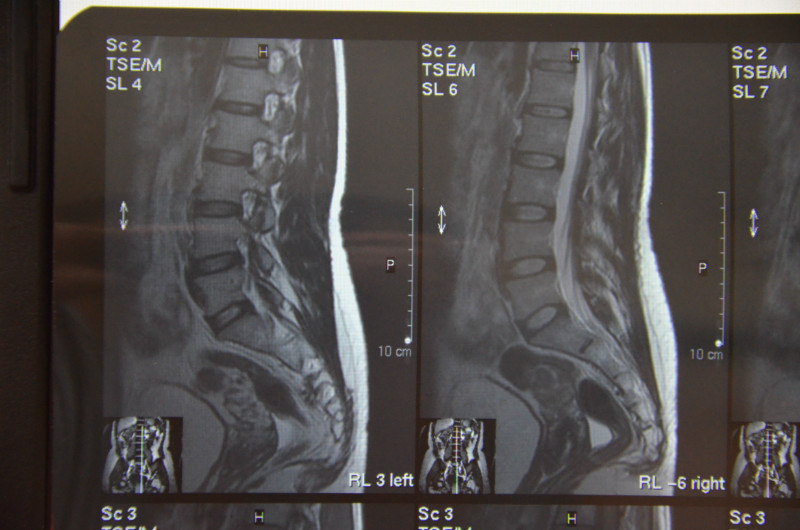

Рентгеновские снимки крестцово-копчикового отдела позвоночника